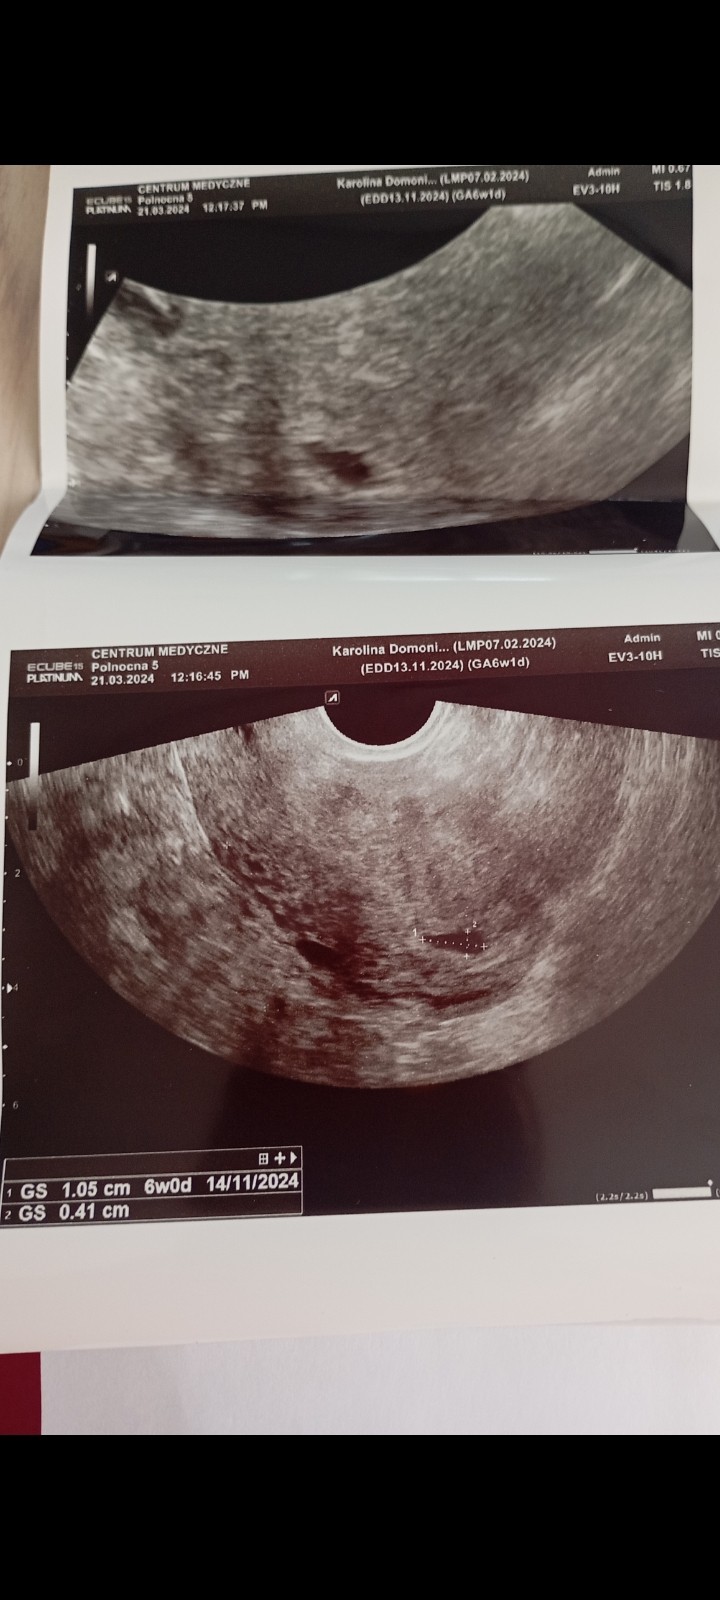

edit. Dojrzałam już na ostatnim zdjęciu GS 1,05cm - także zarodek ma jeszcze czas by się pokazać. Spokojnie czekaj do wizyty za tydzień.

To chyba to 1,05 cm

• Screenshot_2024-03-21-15-31-11-387_com.miui.gallery.jpg

176,7 KB · Wyświetleń: 101